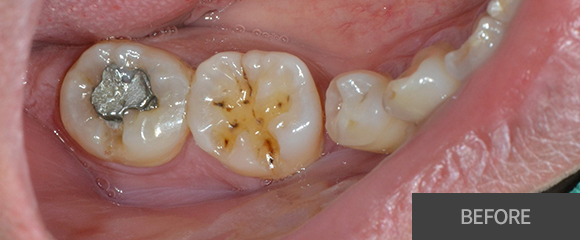

충치치료

레진

인레이

크라운